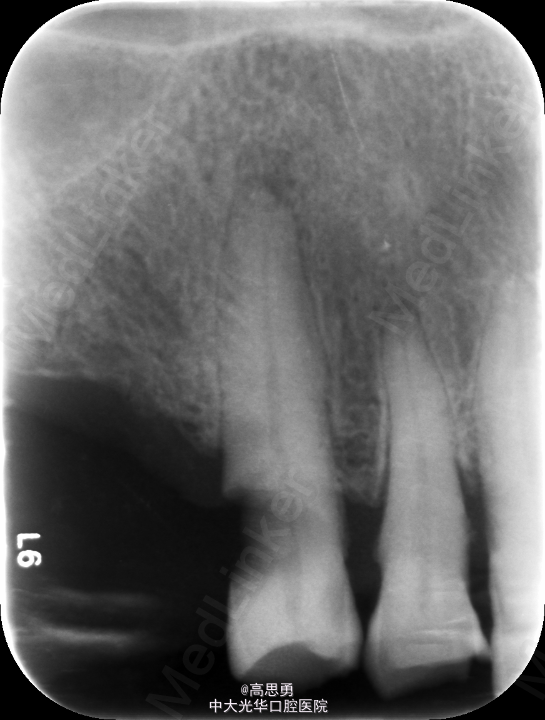

检查(包括专科检查及辅助检查): 1、全身状况良好,无全身系统性疾病,自主行动能力正常。精神心理状态无异常。 2、颌面部左右对称,面部比例协调,面部正面形态尖圆形。颞下颌关节运动无异常,开口型无异常,颞下颌关节无弹性,无压痛。 3、口内黏膜未见瘢痕,舌运动无异常。唇颊系带附着无异常,唾液分泌无异常。 4、牙龈正常,无肿胀无瘘管。 5、口内检查: #32近中移位约1mm,无明显倾斜 #44远中移位约2mm,向缺隙侧倾斜,伸长约1mm 其余缺牙间隙正常 全口牙龈退缩至根颈1/3,牙龈无肿胀无瘘管 上颌缺牙区牙槽嵴无明显吸收、下颌缺牙区牙槽嵴吸收呈低平刃状 口腔卫生状况欠佳、全口牙石多 11 12 13 14 15 16 17 21 22 23 24 25 26 27 视 存 存 存 缺 缺 缺 缺 存 存 存 缺 缺 缺 存 探 - - + - - - - - - - - - - - 叩 - - + - - - - - - - - - - - 松 - - I° - - - - - - - - - - - 楔 O O O - - - - O O O - - - - 31 32 33 34 35 36 37 41 42 43 44 45 46 47 视 缺 存 存 存 缺 缺 缺 缺 存 存 存 缺 缺 存 探 - - - - - - - - - - - - - - 叩 - - - - - - - - - - - - - - 松 - - - - - - - - - - - - - - 楔 - - O - - - - - O O O - - - 根尖X片示:13 根尖部阴影,牙颈部硬组织部分缺损 转诊牙体牙髓科后复诊 修复科第二次就诊口内检查: 11、12、13、21、22、23、33、42、43、44牙颈部见黄色充填物 13 探(-)、叩(-)、松(-),HE面见白色暂封物 口腔卫生状况尚可、牙石少,其余牙叩(-)、松(-) 根尖X片示:13 根尖部阴影,根充可 其余同前

诊断: 1、牙列缺损(上颌肯氏II类I分类,下颌肯氏II类II分类) 2、#13慢性根尖周炎 3、#11、#12、#13、#21、#22、#23、#33、#42、#43、#44楔状缺损 4、慢性牙周炎 治疗计划 1、#13转牙体牙髓科做RCT 2、转牙体牙髓科对#11、#12、#13、#21、#22、#23、#33、#42、#43、#44楔状缺损 充填治疗 3、转牙周科进行牙周洁治 4、择期RPD修复 备选修复方案: 1、#13RCT后截冠后,上下颌覆盖义齿修复; 2、#13RCT后冠修复,上下颌可摘局部义齿修复; 3、#13RCT后树脂充填,上下颌可摘局部义齿修复; 4、#13拔除后,上下颌可摘局部义齿修复。 患者意愿:患者希望尽量保持#13的天然形态,要求费用尽量低,但能恢复正常咀嚼功能。 最终治疗方案:根据患者的年龄、身体状况、治疗周期、经济状况,患者最终选择方案5,即#13RCT后树脂充填,上颌结合卡环式可摘局部义齿修复;下颌可摘铸造支架式局部义齿修复。 治疗过程: 1、临床检查和#13树脂充填 对患者进行全面的口腔检查,用Z350树脂充填#13,调HE,抛光。 2、研究模型 调拌藻酸盐印模材料于2号成品托盘上取上下颌研究模,灌注石膏模型,研究分析、制定治疗计划,并制作个别托盘。 3、基牙预备 对#13近中、#23远中、#27近中、#34近中、#47近中常规制备支托凹,抛光。 4、工作模型 调拌藻酸盐印模材料于个别托盘上。做一定的边缘整塑,取上下颌研究模,灌注石膏模型。 5、试戴支架 检查支架的就位、固位可,无翘动,调HE,抛光,用蜡堤取颌位关系,上颌架,排牙,比色C4。 6、试排牙 检查义齿的就位、固位可,无翘动,观察人工牙的咬合状况,尖窝接触良好,正中颌位能重复,患者无诉不适,面容自然,外观满意。送加工厂充胶制作最终修复体。 7、试戴 检查义齿的就位、固位可,无翘动,咬合关系正确,利用咬合纸检查,上下颌尖窝接触均匀全面,抛光,患者表示满意,嘱注意事项,定期复诊。